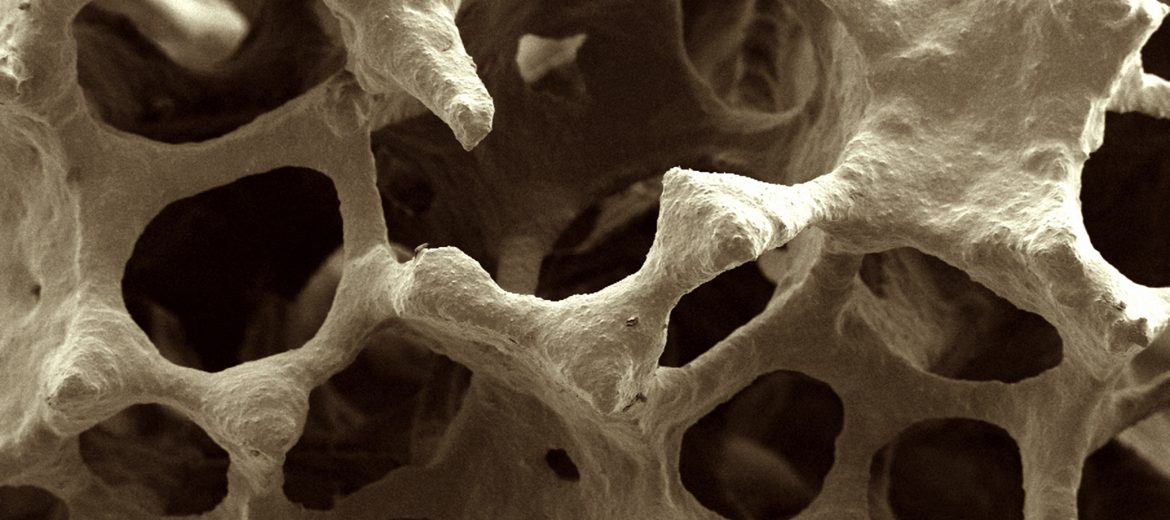

Scanning electron micrograph of bone scaffold imaged at the University of Sydney

Scanning electron microscopy at Microscopy Australia’s University of Sydney facility provided essential information by revealing the structure and biocompatibility of the materials. In-vivo X-ray microtomography at Microscopy Australia at the University of Adelaide enabled the evaluation of the scaffold’s bone-healing potential in animal models.